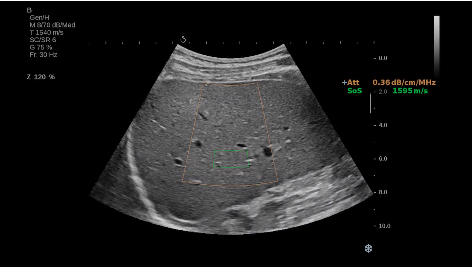

法國聲科影像(SuperSonic Imagine,SSI. Euroniex:FR0010526814)近日發(fā)表公告,宣布其研發(fā)的新一代“極速”超聲成像平臺(UltraFast Imaging),首次實(shí)現(xiàn)了肝臟的多項(xiàng)超聲定量評估新指標(biāo)同步檢測,包括:Att PLUS,SSp PLUS和Vi PLUS等,基本涵蓋肝臟相關(guān)病理變化指征的如纖維化、脂肪變、炎癥等。據(jù)悉,此多項(xiàng)新技術(shù)新將搭載于新Aixplorer系列E超系統(tǒng)。